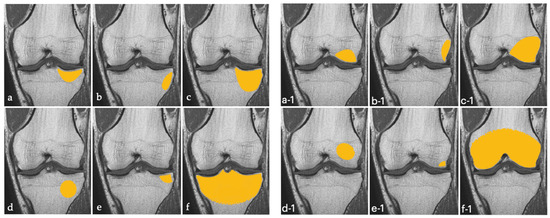

We defined BME of the knee according to the topographic classification proposed by Compagnoni et al., well-illustrated in Figure 2 below [18].

Figure 2.

Schematic illustration of tibial (on the left (a–f)) and femoral (on the right (a-1–f-1)) primary bone marrow edema of the knee, in according to Compagnoni’s classification [18].

Of 5352 patients who were referred to our clinic from 1 January 2015 to 31 August 2021, 330 were diagnosed with BME of the knee and 48 had primary BME of the knee (Figure 3). All had complete bone marrow lesions on MRI, i.e., lesions involving the articular and medial or lateral cortex of the condyle that exceeded 50% of the medial or articular surface or crossed the physis [18].

There was no side predominance in the painful knee. All patients had complete (type C) lesions [18] that involved the medial tibial plateau (43.8%), the lateral tibial plateau (6.2%), the medial femoral condyle (31.2%), or the lateral femoral condyle (18.8%).

All our patients had complete (type C) bone marrow lesions according to Compagnoni et al. [18]. It may therefore be hypothesized that type C primary lesions are more likely to regress with conservative treatment.